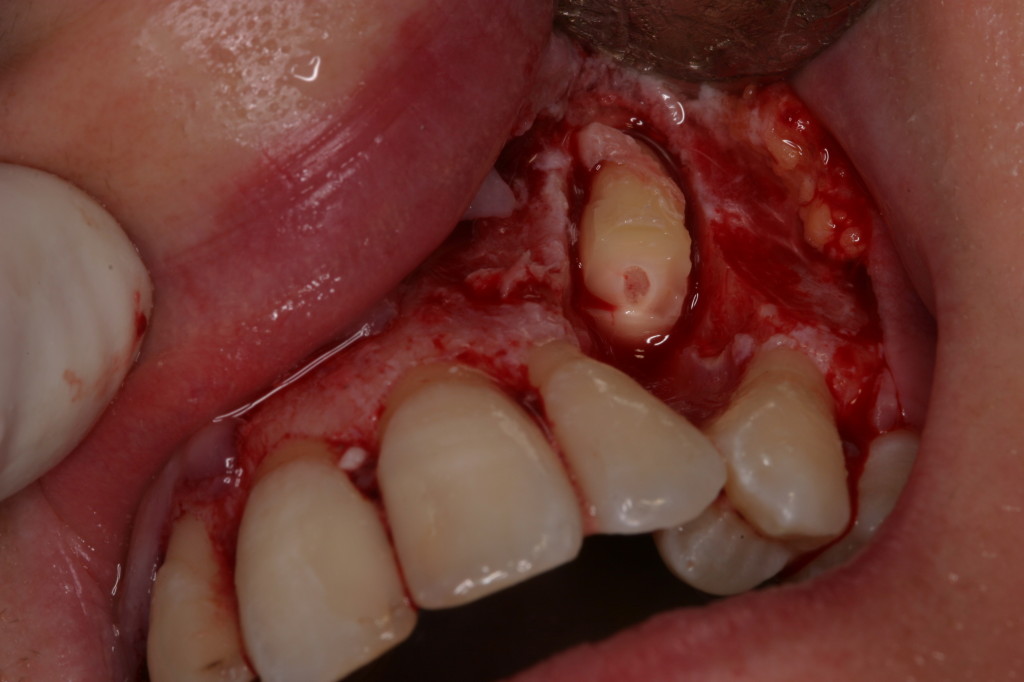

QUISTES EN MOLARES RETENIDOS.

CASO CLÍNICO. APICEPTOMÍA Y QUISTECTOMÍA EN LA PREMAXILA.

CASO CLÍNICO.ENUCLEACIÓN DE QUISTE EN SENO MAXILAR.